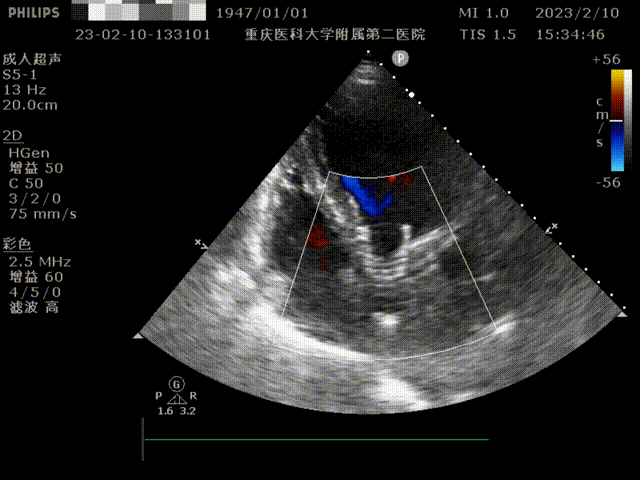

患者为76岁女性,因“反复喘累半月”入院。心脏彩超显示,左房、左室增大,升主动脉增宽,肺动脉增宽。收缩期主动脉瓣口流速350cm/s,平均压差:27mmHg,最大压差49mmHg,舒张期主动脉瓣口左室侧见大量红色为主的花色血流信号,速度438cm/s;EF 48%。诊断主动脉瓣中度狭窄伴重度关闭不全、左房、左室增大、心包积液(少量)、左室收缩功能降低、二尖瓣重度关闭不全、三尖瓣轻度关闭不全。既往患有高血压。

术后超声提示无反流